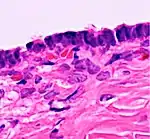

Histopathology

In case an ovarian cyst is surgically removed, a more definite diagnosis can be made by histopathology:

| Type | Subtype | Typical microscopy findings | Image |

|---|---|---|---|

| Functional cyst | Follicular cyst |

|

![]() |